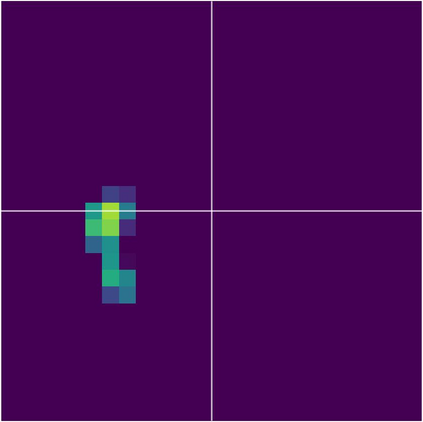

Various imaging modalities allow for time-dependent image reconstructions from measurements where its acquisition also has a time-dependent nature. Magnetic particle imaging (MPI) falls into this class of imaging modalities and it thus also provides a dynamic inverse problem. Without proper consideration of the dynamic behavior, motion artifacts in the reconstruction become an issue. More sophisticated methods need to be developed and applied to the reconstruction of the time-dependent sequences of images. In this context, we investigate the incorporation of motion priors in terms of certain flow-parameter-dependent PDEs in the reconstruction process of time-dependent 3D images in magnetic particle imaging. The present work comprises the method development for a general 3D+time setting for time-dependent linear forward operators, analytical investigation of necessary properties in the MPI forward operator, modeling aspects in dynamic MPI, and extensive numerical experiments on 3D+time imaging including simulated data as well as measurements from a rotation phantom and in-vivo data from a mouse.